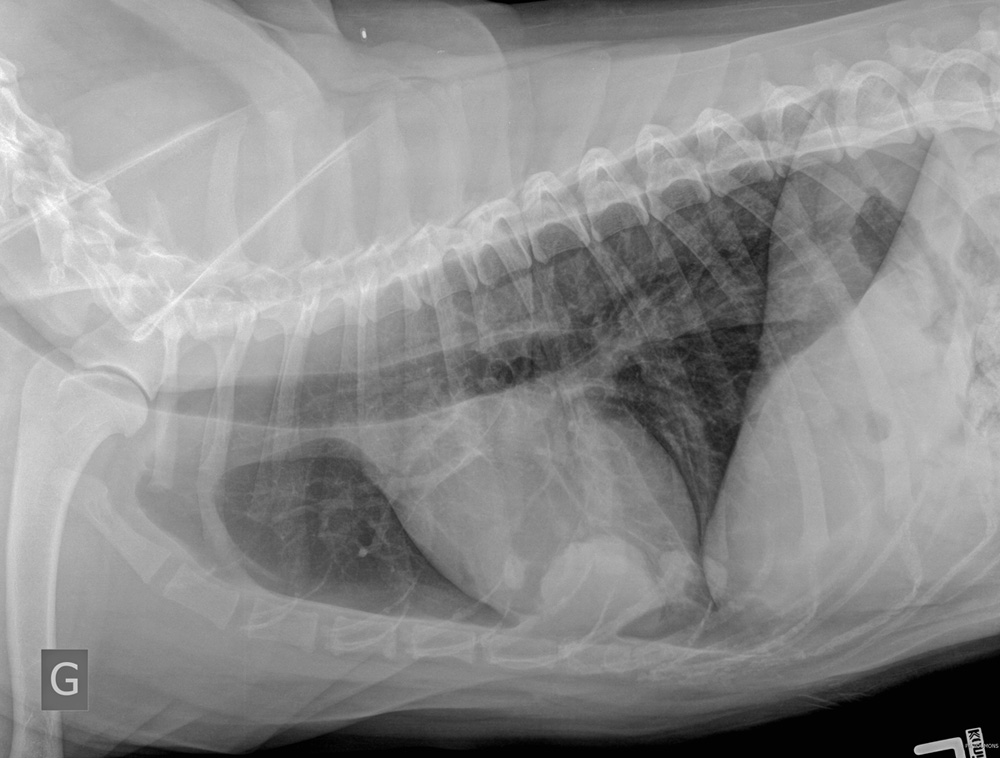

À la demande populaire, on a obtenu une latérale gauche. La voici !